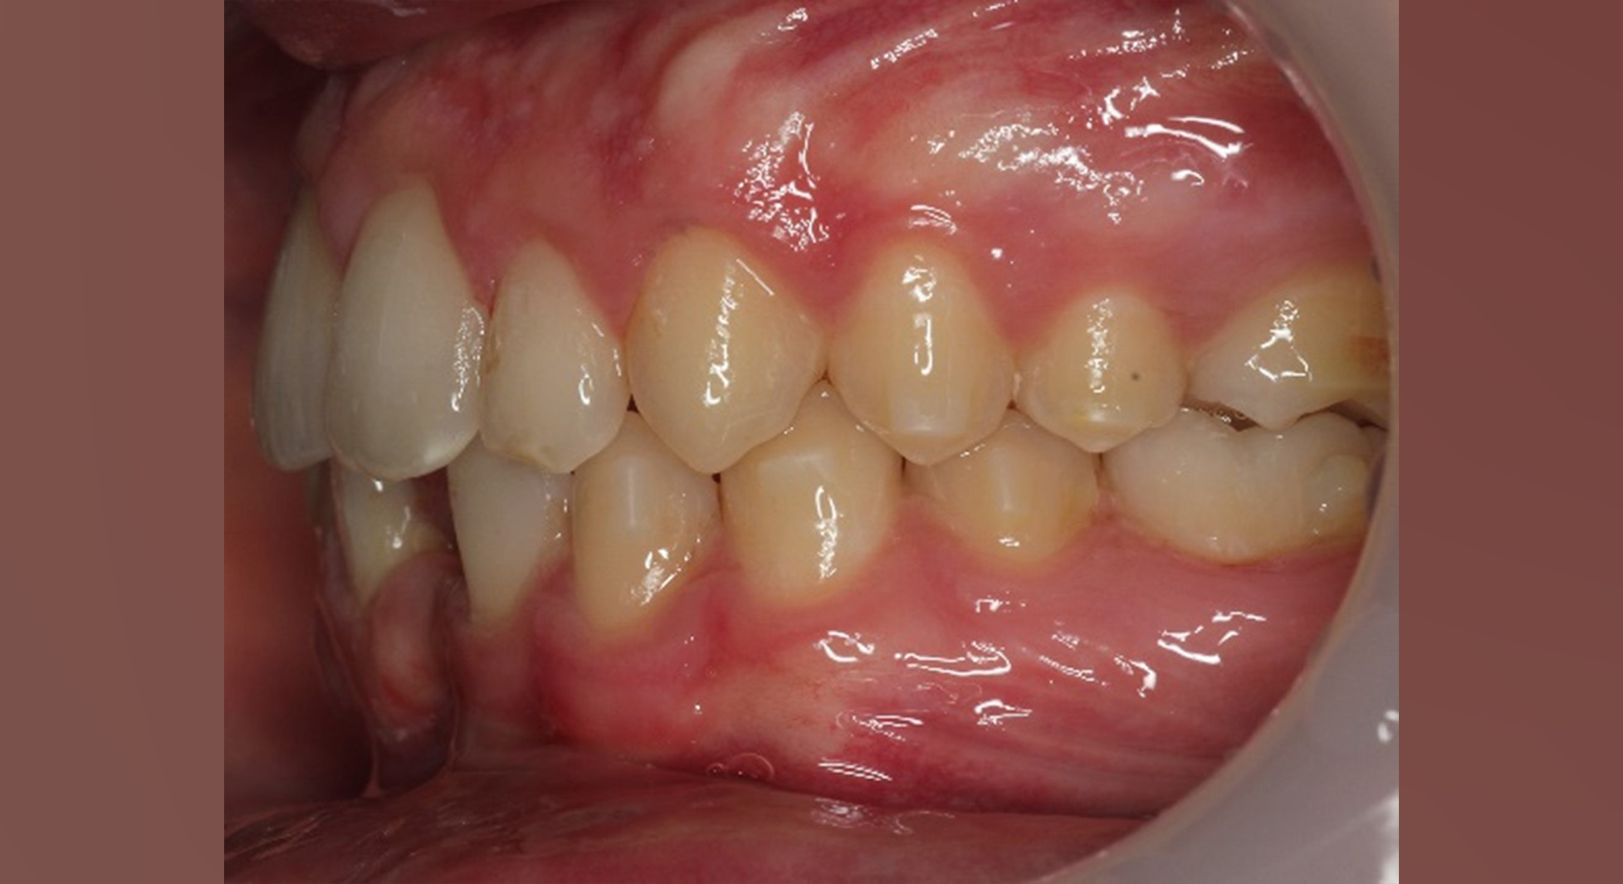

Skeletal Class II due to mandibular retrognathia, proclination of maxillary incisors, narrow arch creating a V-shaped arch, agenesis of 12, 31, 41, hyperdivergent facial pattern, moderate deep bite (2 mm), increased overjet (9 mm), asymmetric canine and molar Class II due to mandibular deviation to the left, maxillary midline deviation related to agenesis of 12, distal rotation of 35 and 45, and pronounced lower curve of Spee.

Elastics protocol

Class II elastics: 4.5 oz, 14 hours/day

Hooks on 13 and 23, button cut-outs on lower molars